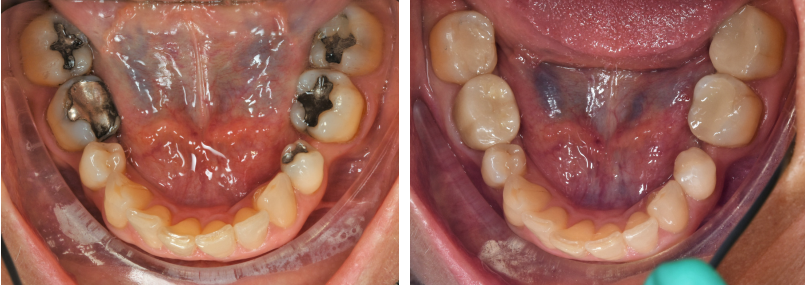

Before and After Mercury Amalgam Removal